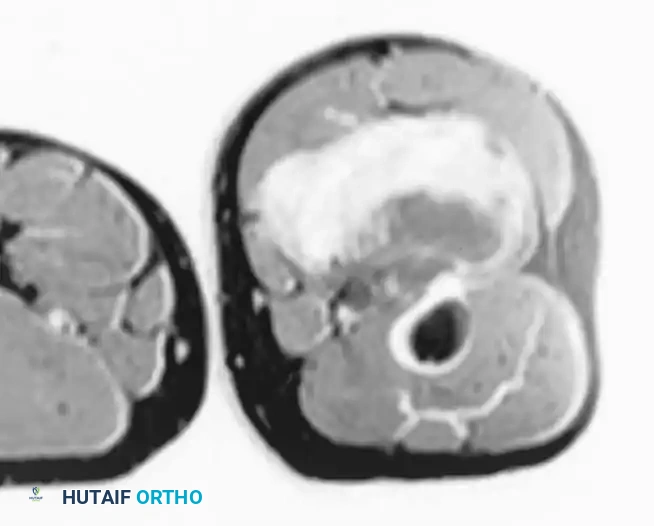

Imaging:

MRI is highly specific for well-differentiated variants, demonstrating fat signal intensity (bright on T1, suppresses on STIR/Fat-Sat) with thick, nodular septations.

T1-weighted MRI of a well-differentiated liposarcoma (atypical lipoma) of the thigh.

Contrast-enhanced, fat-suppressed axial MRI of the same lesion. Note the multiple thick, enhancing septa distinguishing it from a benign lipoma.